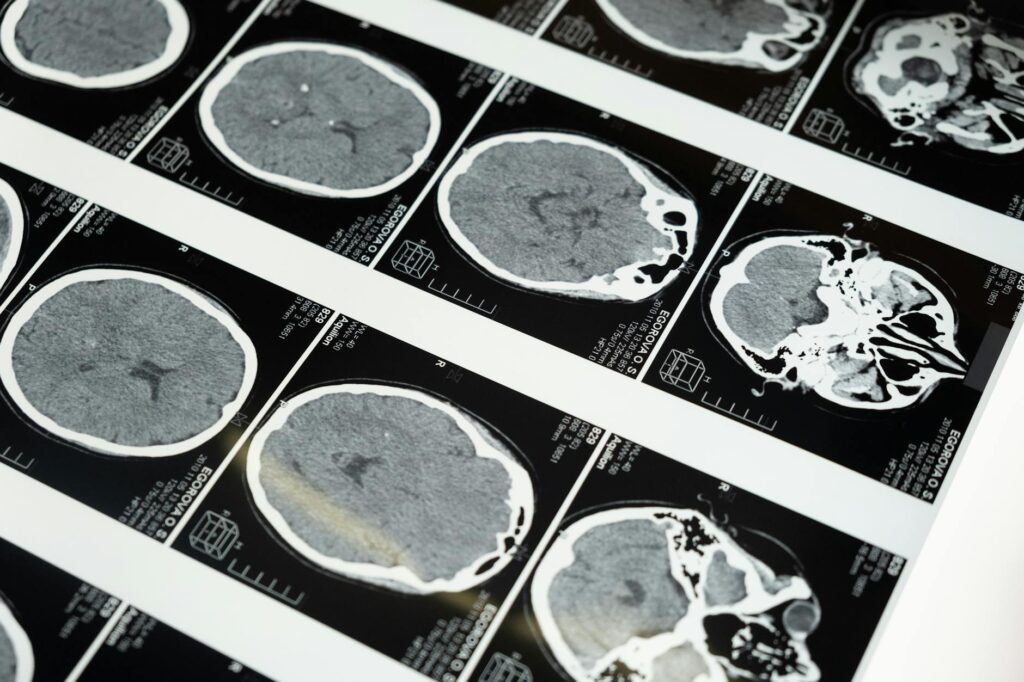

- Radiology Reports: Imaging results that provide information about a patient’s condition.

For an injury claim, you typically need comprehensive medical records, including diagnosis reports, treatment history, prescription records, and any imaging studies like X-rays or MRIs. Additionally, documentation of medical bills and any notes from healthcare providers regarding the injury’s impact on your daily activities can further strengthen your claim.